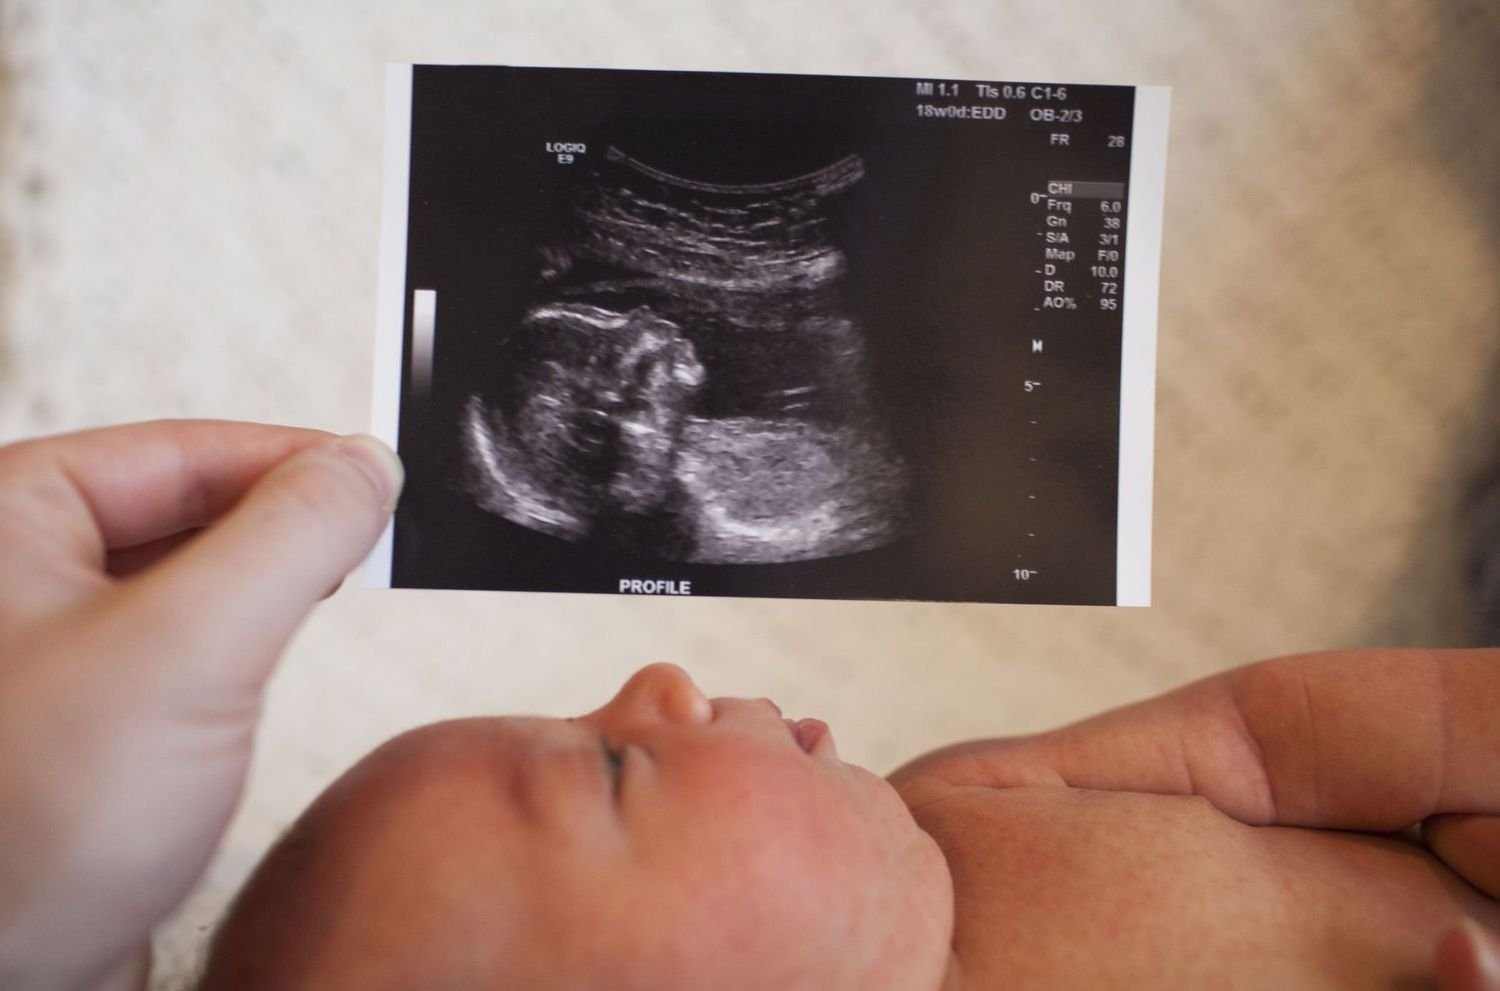

We provide quick and accurate Emergency Sonography, X-Ray, and Doppler services for immediate diagnosis.